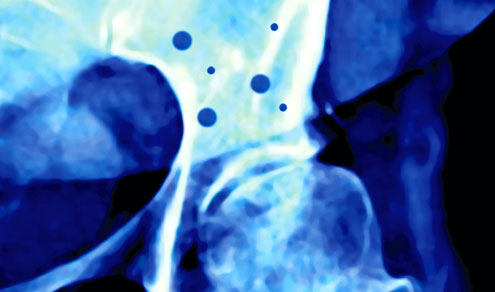

O controle da doença é feito por meio de exames laboratoriais e da densitometria óssea, que consegue medir exatamente a quantidade de cálcio perdida e a evolução da recuperação óssea.